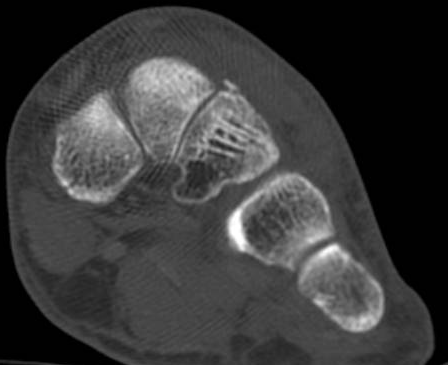

ÄÄÇ»ÅÍ ÃÔ¿µ : Á¾°ñÀÇ °ñÀý , µÎ ºÎÀ§(÷ºÎ ÆÄÀÏ Âü°í)

ÄÄÇ»ÅÍ ÃÔ¿µ ÆÇµ¶¿¡¼­ Á¾°ñÀÇ µÎ ºÎÀ§ °ß¿­°ñÀýÀÌ ¾ð±ÞµÇ¾úÁö¸¸ ÃÊÀ½ÆÄ°Ë»ç»ó  Ãß°¡ÀûÀÎ °ñÀýÀ»

È®ÀÎÇÒ ¼ö ÀÖ¾ú´Ù.

ÄÄÇ»ÅÍ ÃÔ¿­»óÀÇ °ñÀý ºÎÀ§´Â ÃÊÀ½ÆÄ°Ë»ç¿¡¼­ È®ÀÎÇÒ ¼ö ÀÖ¾ú°í »çÁø 10~15¿¡¼­ È®ÀÎÀÌ °¡´ÉÇÏ´Ù.

Á¾°ñÀÔ¹æ°ñ°üÀý Á¾´Ü¸é°Ë»ç»ó Á¾°ñ Àü¹æµ¹±â °ß¿­°ñÀý°ú Á¦4ÁßÁ·°ñ °ß¿­°ñÀýÀÌ °üÂûµÈ´Ù(»çÁø 2).